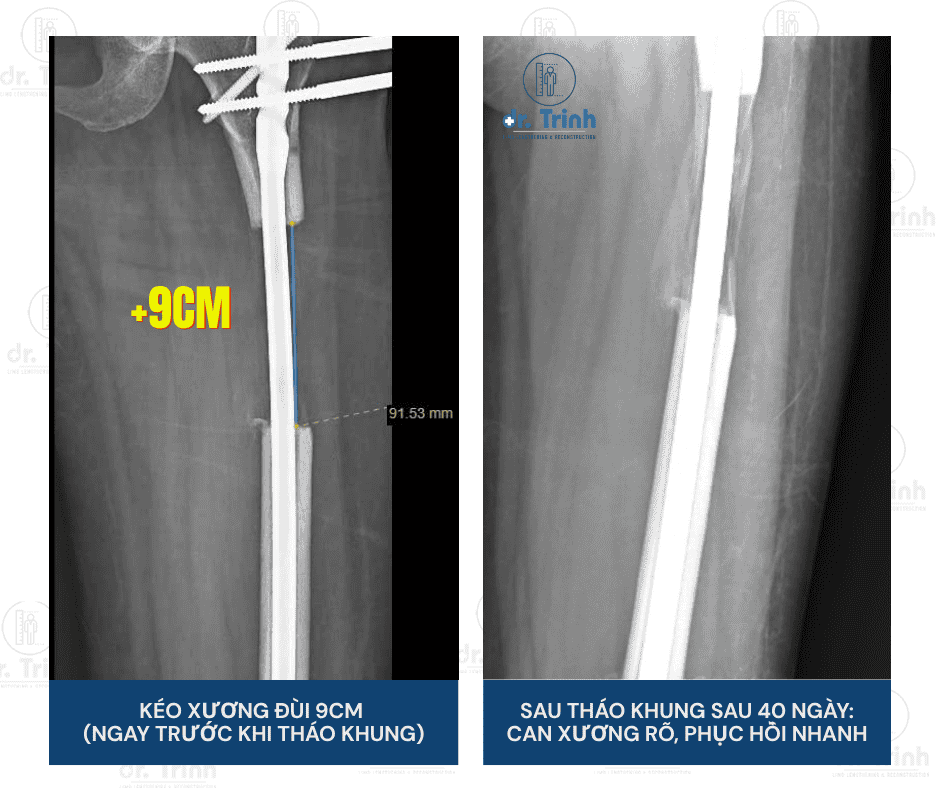

Bác sĩ đã thực hiện phẫu thuật kéo dài xương đùi cho một bệnh nhân nữ, 30 tuổi, với mục tiêu tăng chiều cao lên tới 9cm – đây là một mức kéo khá lớn.

Chỉ sau 40 ngày, hình ảnh X-quang cho thấy can xương đã hình thành rõ ràng, cho thấy tốc độ liền xương rất tích cực. Nhờ vào quá trình luyện tập kiên trì và tinh thần hợp tác tốt của bệnh nhân, chỉ chưa đầy 2 tháng sau mổ, bạn nữ đã có thể đi lại nhẹ nhàng, dần quay trở lại nhịp sống bình thường.